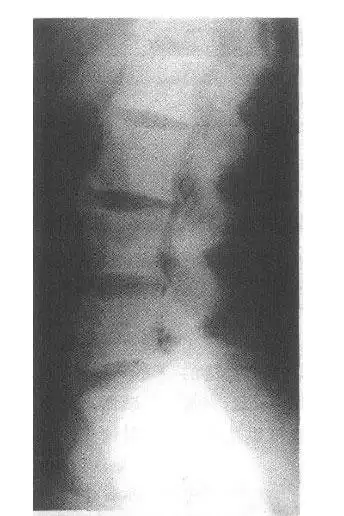

冠状位腰椎ct平扫.